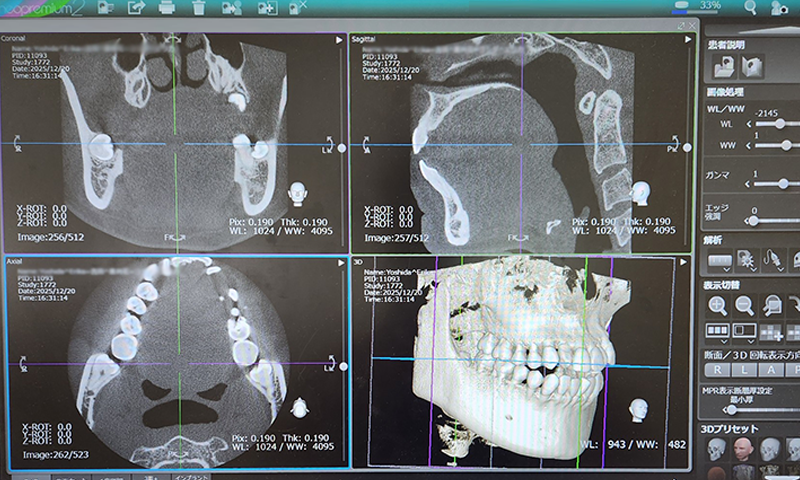

歯科用CT

歯科治療で求められる多彩な画像診断ニーズに、独自の技術と豊富なノウハウで応えた先進のオール・イン・ワン・システムです。

特に、需要の高まるCT撮影においては、高域な撮影範囲と、患者さんにやさしく正確なポジショニングシステムで、精緻な画像診断を実現します。